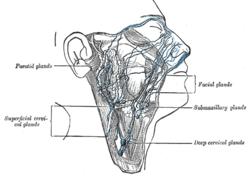

Superficial lymph glands and lymphatic vessels of head and neck.

The lymphatics of the face.